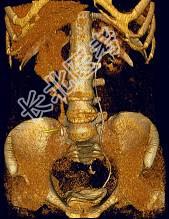

- 多项选择题患者女,44岁, 突发性胁腹部绞痛并向会阴部放射伴血尿一次。如图所示,下列说法正确的是 ( )

A、右侧肾盂肾盏扩张

B、右输尿管中上段扩张

C、右输尿管内可见沿输尿管走行的高密度影

D、右输尿管结石

E、左肾输尿管未见异常